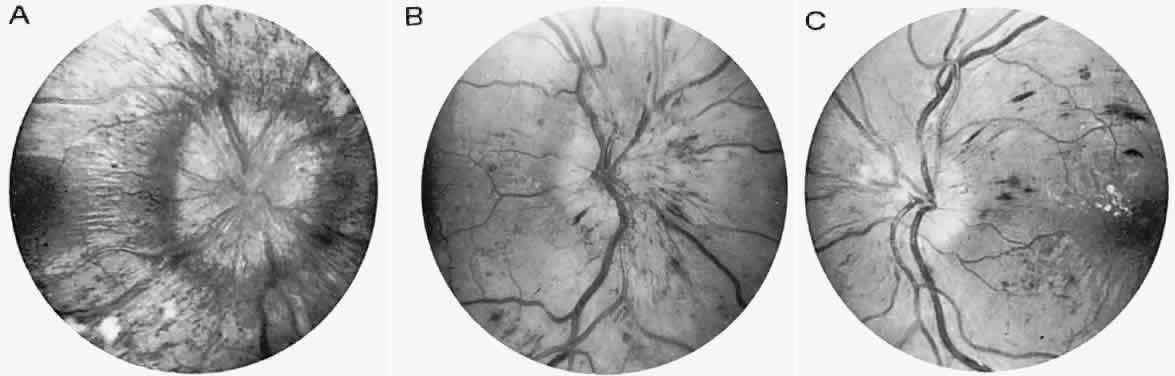

Atypical cases of selective pigmentary degeneration of the nasal retinal sectors (Fig. 2) produce field defects that may mimic bitemporal hemianopias. Such preferential involvement of the fundus nasal to the optic disc occurs in at least one-third of patients with sectoral retinitis pigmentosa. Nerve fiber bundle scotomas, somewhat mimicking glaucoma, are also recorded.7,8

Fig. 2. Retinitis pigmentosa. A. Advanced field loss showing dense annular defects. Deficits start in the 20° to 30° middle zone (as compared with Bjerrum's zone defects in glaucoma) and proceed toward fixation and outward toward the periphery. Central fixation is relatively spared, producing “gun-barrel fields.” B. The pseudobitemporal field defects of sector retinitis pigmentosa. Unlike chiasmal interference, the defects cross the vertical meridian. C. Left fundus of patient with nasal-sector retinitis pigmentosa.

Central field defects with acuity loss occur with photoreceptor degeneration that especially affects the macula, so-called retinitis pigmentosa inversa, but this disorder likely represents a separate nosologic class, the cone-rod dystrophies (see below) (Fig. 3). Severe visual defect in early infancy is frequently enough caused by a primary outer segment retinal abiotrophy, Leber's congenital amaurosis, although this is probably not a single clinical entity. This disorder is characterized by the following: severe impairment of vision, present at birth or becoming evident during early to late infancy; a fundus that may initially approach normal, but within years, optic atrophy, diffuse fine pigmentary degeneration, and attenuation of the arteriolar tree are evident; and either an absent or a markedly reduced ERG response. Other variable features include nystagmus, photophobia, digito-ocular maneuver (forceful eye rubbing with sunken globes; “blindisms”), strabismus, cataracts, hyperopia, mental retardation, deafness, renal anomalies, seizures, hydrocephalus, and focal neurologic deficits (e.g., cerebral diplegia). Hereditary transmission is typically autosomal recessive10 (see Volume 2, Chapter 13).

Fig. 3. Cone-rod dystrophy or so-called “retinitis pigmentosa inversa” in a young man with progressive spinocerebellar degeneration and 20/200 acuity in each eye.